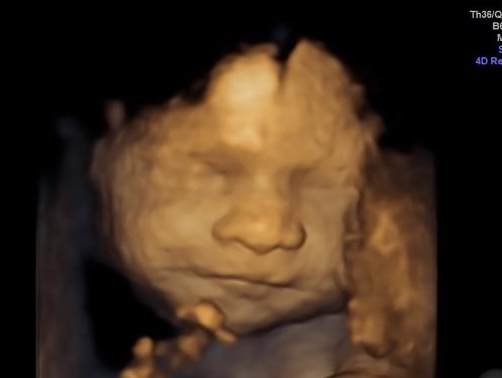

From tiny smiles to playful tongue movements, babies make fascinating expressions even before they are born. Thanks to advanced prenatal imaging, parents can now witness these moments in stunning detail.

But what do these 4D ultrasound expressions mean? Let’s explore the science behind these adorable gestures and their role in a baby’s development.

Scientists believe that facial expressions in the womb are more than just random movements. They are signs of early neurological and muscular development. Around the 24th week of pregnancy, babies start developing the ability to make facial movements, which gradually become more refined. By the third trimester, their expressions resemble those of newborns!

Expectant parents cherish the opportunity to see their little one’s first expressions. Unlike traditional scans, a baby 3D ultrasound image provides a detailed view of a baby’s face, while a 4D ultrasound captures real-time movements. These advanced prenatal imaging services allow families to bond with their babies before birth and create lasting memories.